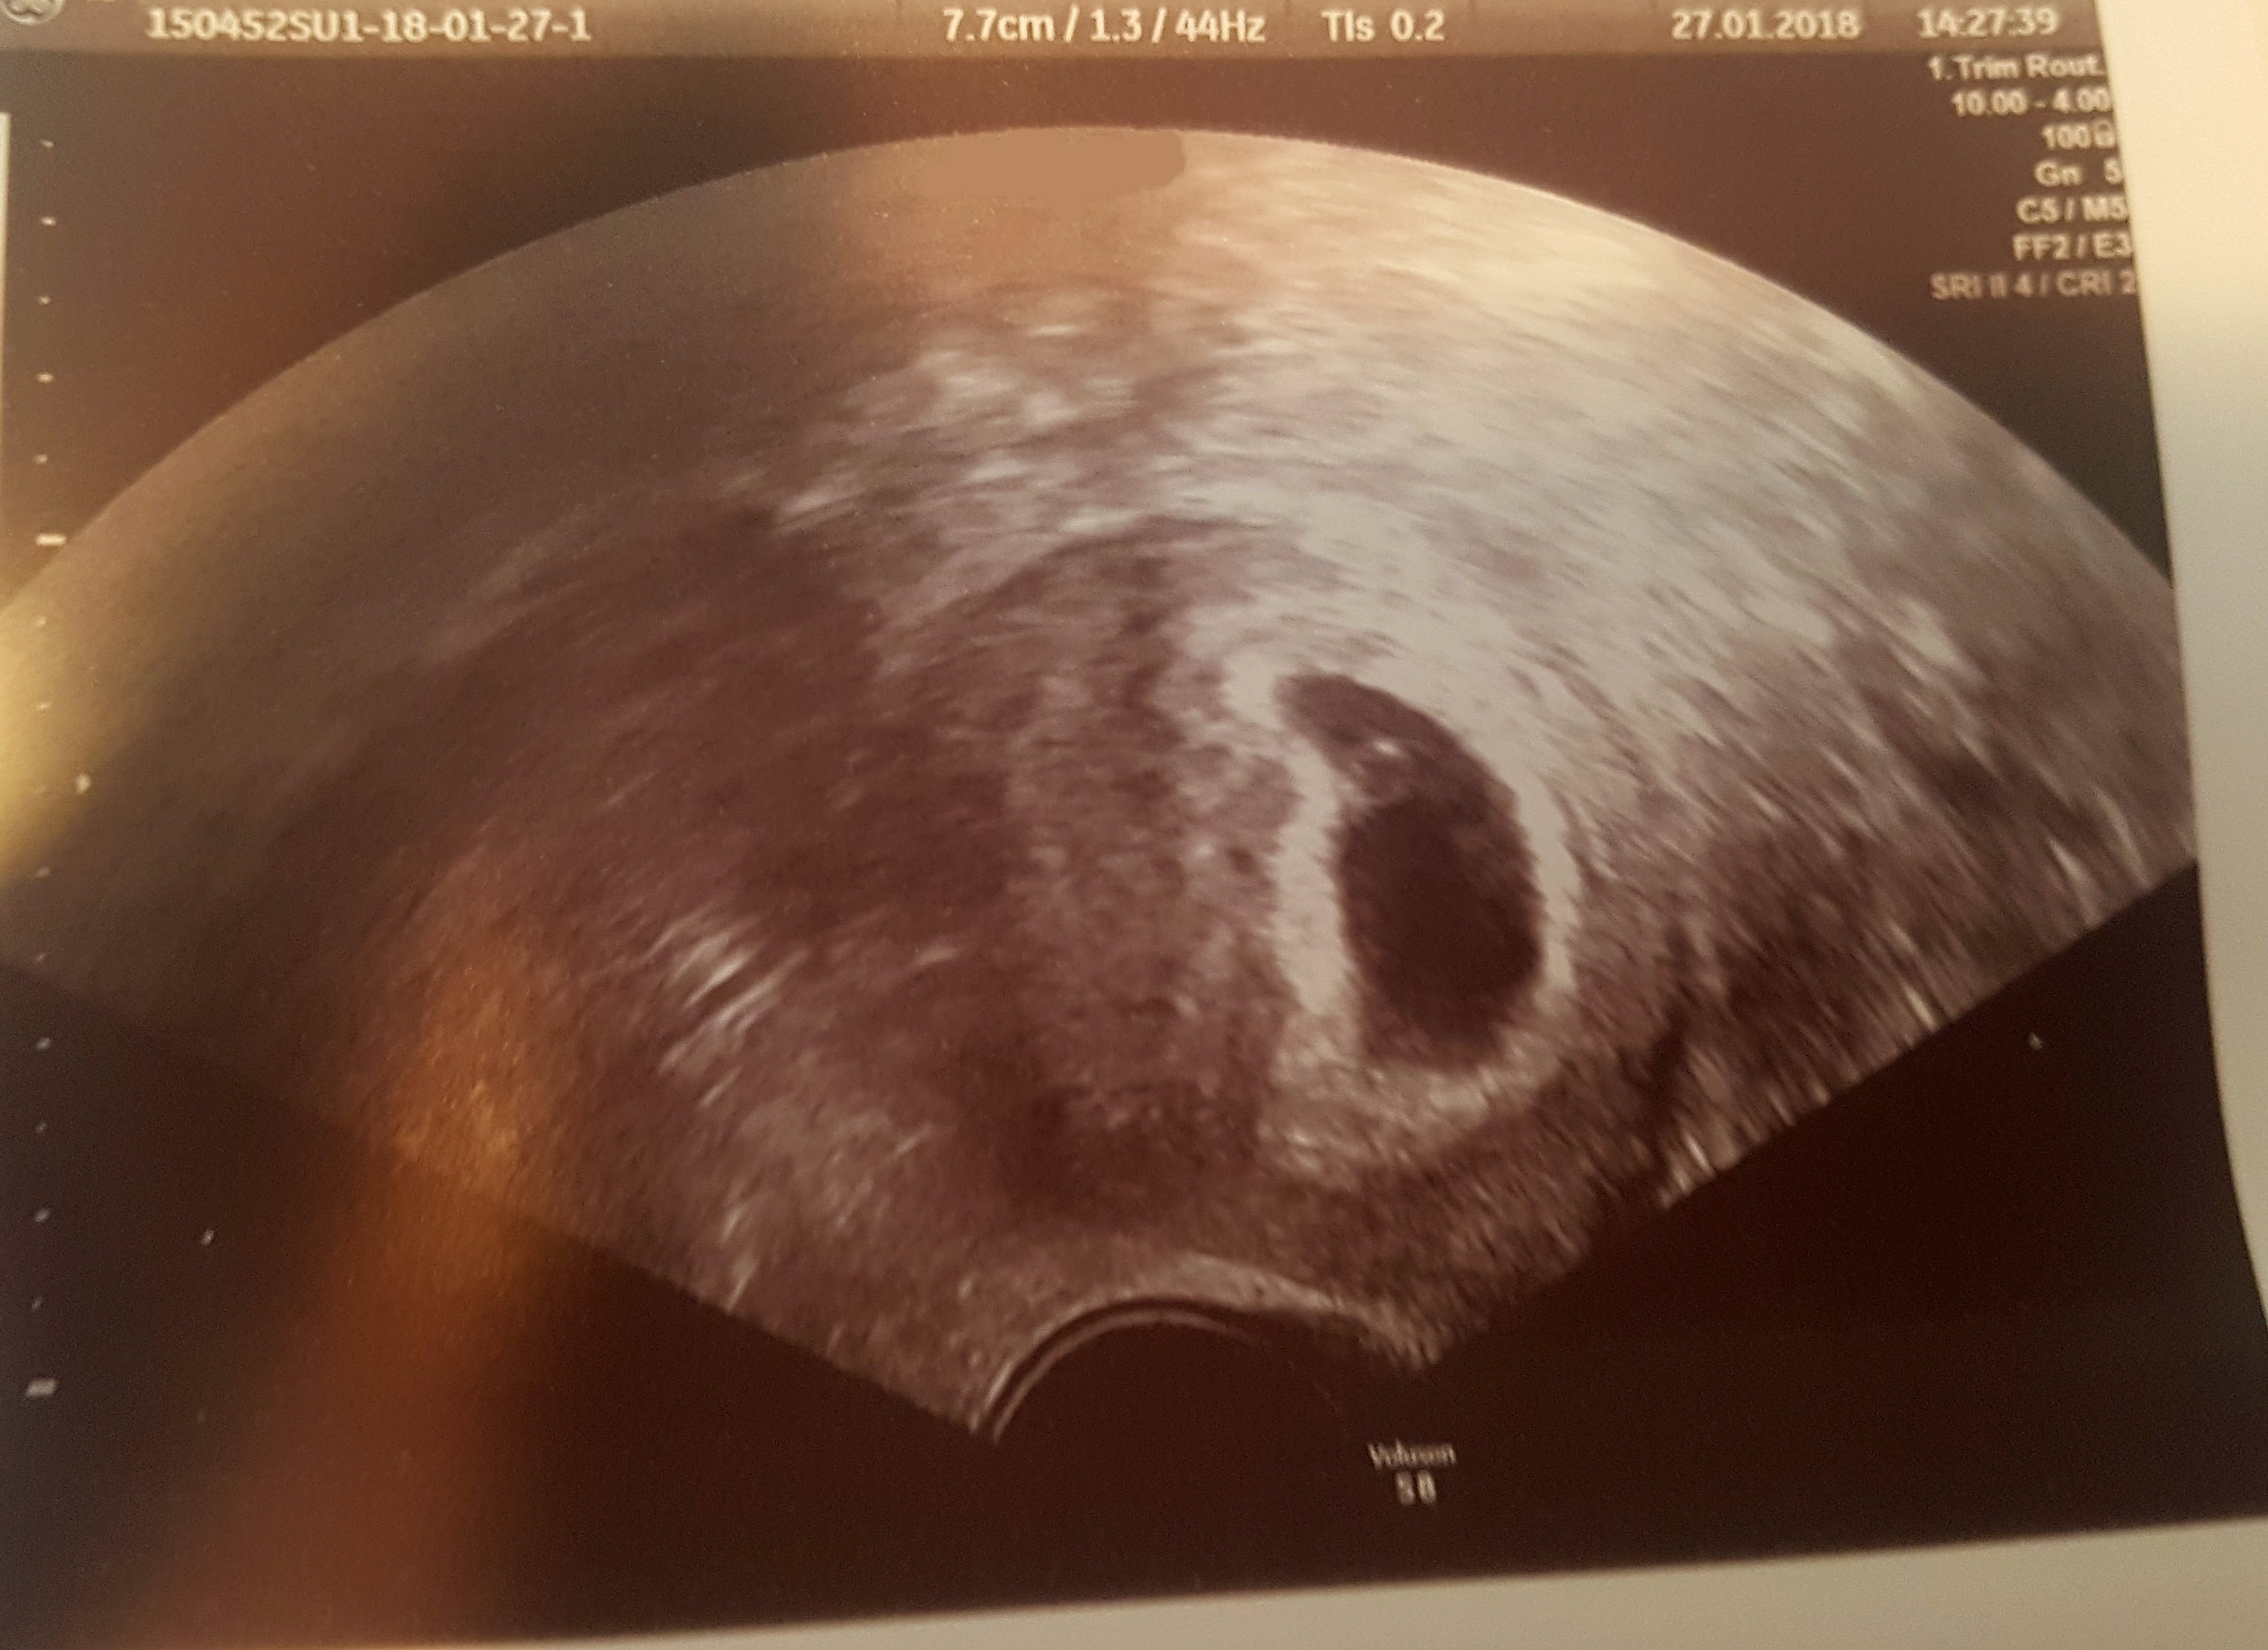

Mein hcg wert war am Donnerstag noch bei 2, sollte also mittlerweile bei 0 sein Also kann auch bald wieder der zyklus starten Meine Frage ist jetzt, wie lange es bis zum nächsten Eisprung dauert sobald kein hcg mehr im Körper ist Hat man dann relativ direkt wieder einen Eisprung oder dauert das dann nochmal einige Wochen?. Hcg wert nach fehlgeburt wieder schwanger HCG Wert nach fehlgeburt Hallo, Vor 5 Wochen wurde meine Fehlgeburt 12 Woche (Embryo auf dem Stand der 6 Woche, nur Fruchthöhle ist weitergewachsen) mit Cytotec beendet Das hat auch gut geklappt Am Samstag wurde noch einmal den HCG Wert bestimmt und der ist leider immer noch bei 600. Ich hatte am einen missed abort mit Ausschabungnun bin ich wieder schwanger!.

Wann der nächste Eisprung nach der Fehlgeburt ist, ist individuell von Frau zu Frau unterschiedlich Erfolgte nach der Fehlgeburt eine Ausschabung , um Reste des Embryos aus der Gebärmutter zu entfernen und Blutungen vorzubeugen, dauert es bei einigen Frauen noch ein wenig, bis der nächste Eisprung einsetzt. Ich hatte am 2710 ein termin beim frauenarzt mein test war positiv aber hatte blutungen nach 2 wochen bekommen da haben die blut abgenommen und mein hcg wert war 631 nach eine woche haben die mir nochmal blutabgenommen und der wert war 371 hab keine blutungen mehr Was kann das bedeutet hab morgen noch einmal ein termin. Ich wäre errechnet heute bei 45 ssw!.